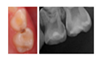

- Case 3: proximal carious lesion on a first primary molar (74, likely ICDAS 4, detected in bitewing radiograph as D2 lesion) in an elementary schoolchild;